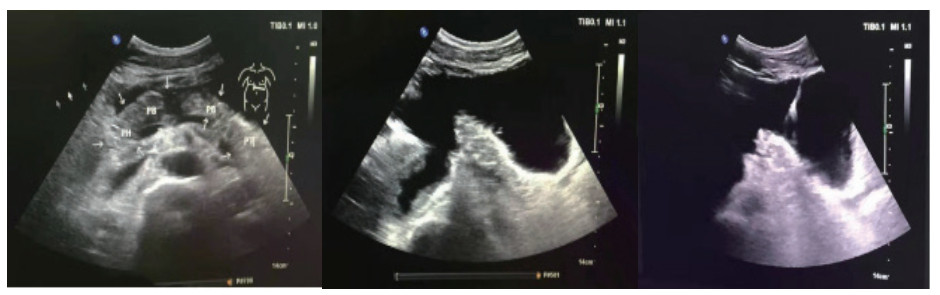

患者男,26岁,维吾尔族,以“高处坠落致腹部疼痛2 d”为主诉入院。患者于2019-03-26凌晨1时左右饮酒后不慎从2 M高处楼梯上摔下,伤及头部、腹部及腰背部,左侧面颊部见少量出血,当时神志状态不明,是否存在腹部及腰背部疼痛,无人知晓。至清晨8时左右,被家属发现俯卧于楼梯口,患者昏睡,周围未见呕吐物,楼梯上可见少量血迹,面颊部擦伤已结痂,呼唤能醒,自诉腹部及腰背部疼痛不适,无头痛、头晕,无恶心、呕吐,遂被立即送往当地县人民医院,CT检查后考虑“胰腺断裂”,给予输液治疗(具体不详),患者意识逐渐转清,可简单对答。为进一步治疗,于2019-03-26晚21:45转入阿克苏农一师医院。入院查体:体温37.1℃,呼吸20次/min,心率90次/min血压120/79 mmHg,腹部平坦,腹皮肤表面未见明显挫伤痕迹,未见胃型,未见肠型,未见蠕动波,无腹壁静脉曲张,未见手术瘢痕,全腹压痛,腹肌紧张,上腹部明显,反跳痛全腹存在,未触及液波震颤,未及腹部包块,肠鸣音减弱,1~2次/min。双肾区有叩痛,右侧明显。骨盆挤压试验(-)。急诊检查生命体征尚稳定,拟诊“腹部闭合性损伤:胰腺断裂?右肾动脉损伤、右肾坏死?”收入ICU。入院诊断:闭合性腹部损伤,胰腺断裂Ⅳ级(主胰管断裂)、弥漫性腹膜炎、右肾动脉损伤、右肾梗死。入院实验室检查:WBC:11.5×109/ L, N:92.1%, Hb 10.5 g,PCT:4.32 ng/mL。入院影像学检查:胸部+腹部增强CT(2019年3月2号晚21:45):右肺下叶炎症,右侧胸腔少量积液,双侧局部胸膜肥厚,胰腺断裂伴周围低密度病灶,考虑假性囊肿形成,右肾动脉损伤,右肾无灌注,腹腔、盆腔积液(考虑血性),腹腔内局部脂肪间隙浑浊,考虑腹膜炎,提示:腹腔内部分肠管明显扩张并积气。此报告为危急值报告!治疗经过:入住ICU,先期放置胃管行胃肠减压,4 d后起经鼻空肠营养,逐渐加量至全量;主要药物泮托拉唑抑酸护胃,生长抑素抑制胰酶分泌,头孢他定+甲硝唑抗感染;本案例入院时创伤发生已过24 h,右肾不显影提示肾动脉梗死造成右肾梗死,介入再通已过时间窗,故放弃介入,不做进一步处理;入院当天腹部增强CT提示胰腺断裂Ⅳ级,胰管完全离断,胰头与胰体尾明显分离,腹腔积液以左中上腹、左下腹居多,腹膜刺激征遍及全腹,按传统观点手术指征明确。但血流动力学稳定,读CT片并完成MRCP后,排除空腔脏器破裂,明确积液集中于上腹部和左下腹,大胆尝试在创伤ICU支持下行非手术治疗。2019-03-29患者行B超检查,示腹腔积液,积液相对集中于左中上腹和左下腹(图 1)。B超定位引导下行左上腹和左下腹穿刺引流(图 2),引出液体性状淡血性,引流效果明显,患者病情较前好转,但血象仍较高,予头孢他啶和甲硝唑抗感染。入院4 d后腹胀缓解即行经鼻空肠营养,以后视腹胀情况逐日加量,5 d后出ICU,因经济问题普通病房住院10 d,带管出院。出院1个月后来院行ERCP术置管困难,放弃置管内引流,继续腹腔引流管回家,未做任何处理。3个月后腹腔引流管自行脱落,6个月后来院复查CT(图 3),胰腺外形基本恢复正常,腹腔无积液,饮食正常,自诉家中腹腔引流管脱落后无任何不适。

图 1 患者入院48 h后胰腺彩色超声影像:肠间有积液

图 2 患者左中上腹部和左下腹穿刺引流